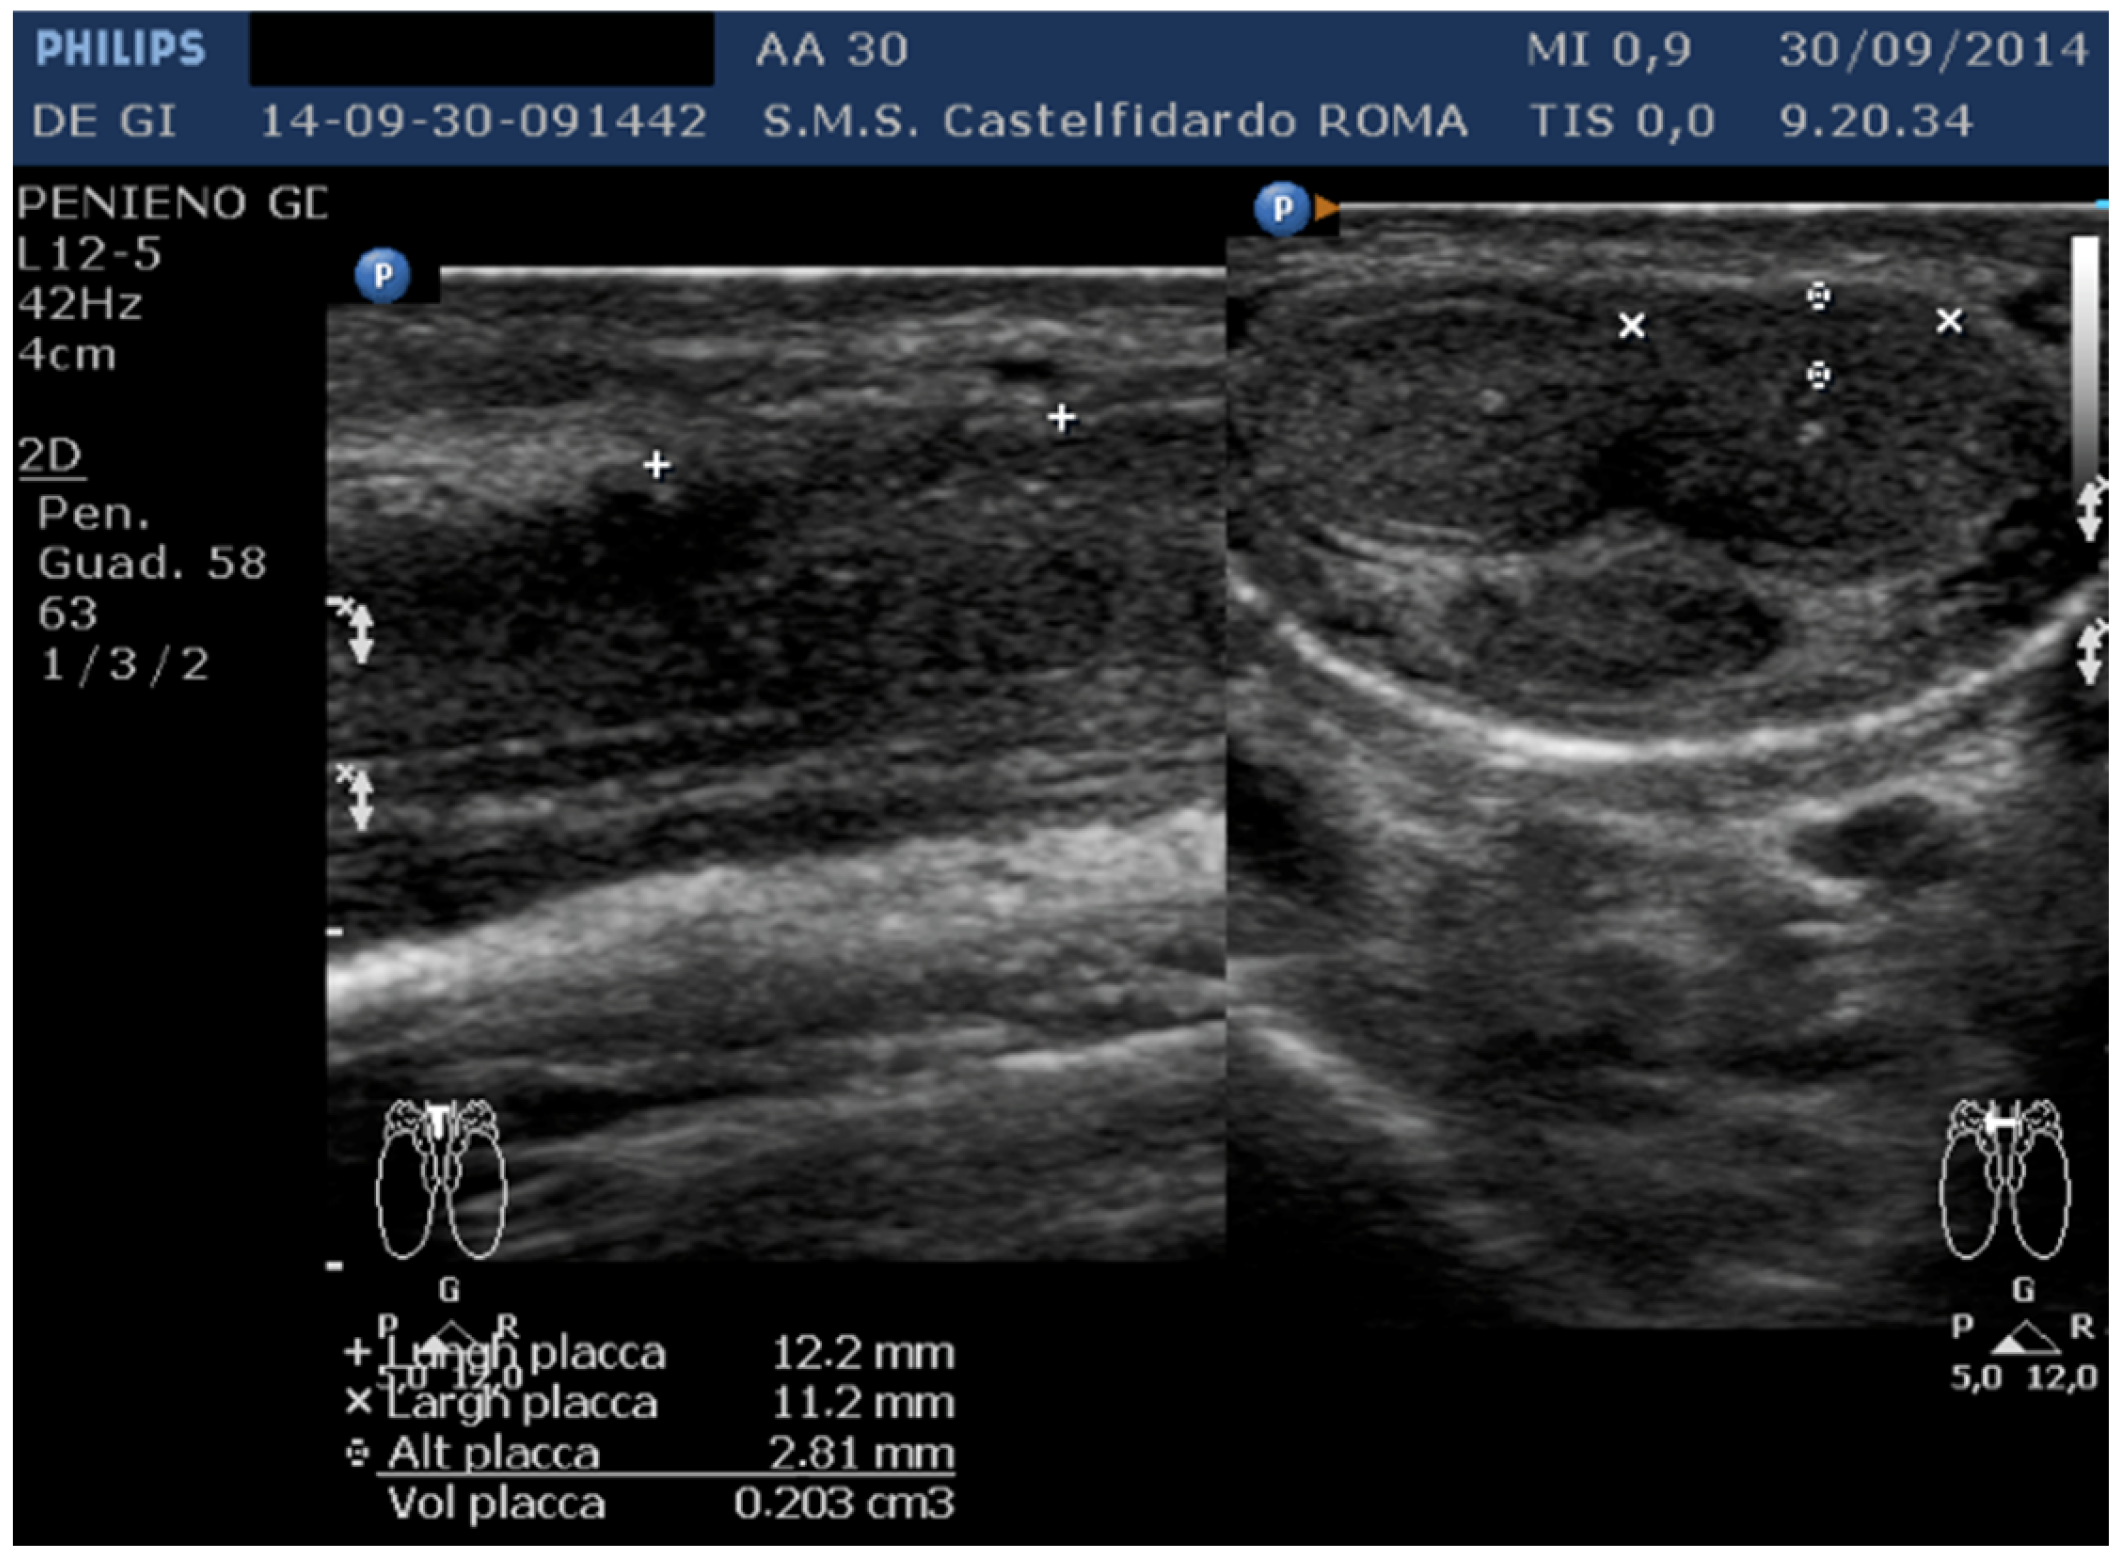

| No. | Patient Age | Associated Disease | Penile Plaque Site | Ultrasound Measurements (Length × Width × Thickness) and Plaque Volume before (A) and after Treatment (B) | Type of Deformity Initial (A) and after Treatment (B) | Pain Score/VAS Scale (1–10) | IIEF Score before and after Treatment | Total Duration of Treatment until Plaque Regression | Complete Combined Multimodal Treatment |

|---|---|---|---|---|---|---|---|---|---|

| 3 | 30 years | Left varicocele | Proximal third | (A) 12.2 × 11.2 × 2.81 mm volume = 203 mm3 (B) No plaque detected | (A) No penile deformation (B) No penile deformation | VAS score = 5 Pain disappeared after 4 months | 26 > 26 | 4 months | Orally: propolis 600 mg + bilberry 160 mg + silymarin 400 mg + ginkgo biloba 250 mg + vitamin E 800 IU/daily for 4 months + topically: diclofenac gel 4%/2× daily for 4 months Note: Penile injections not needed |